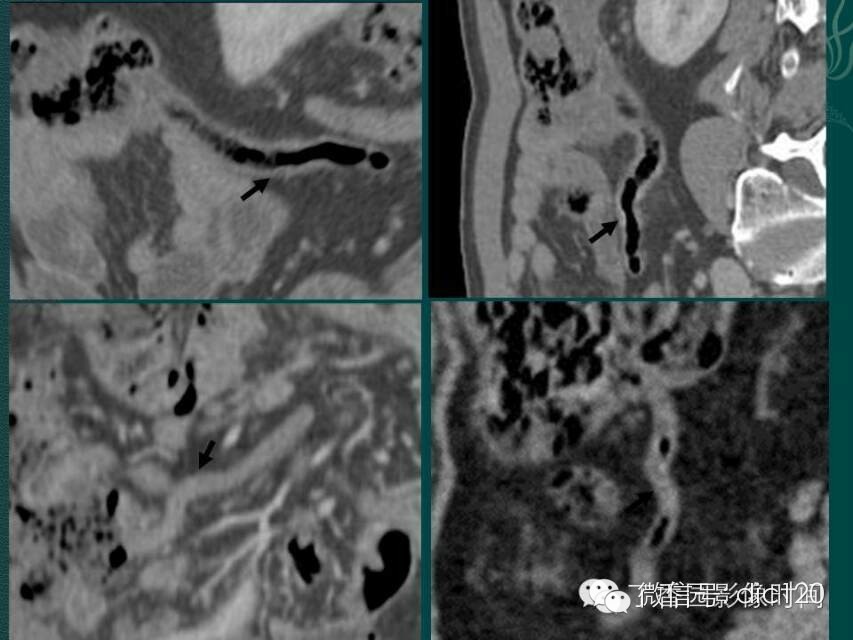

急性阑尾炎的MSCT诊断